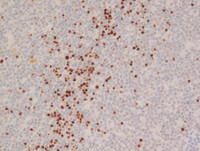

Figure 3 Immunostains LEF1, cyclin D1, Ki67, p53, bcl2

LEF1 immunostain (top left image) at high power view showing lack of staining for LEF1 in  lymphoma cells. The positive staining for LEF1 is seen in the scattered normal T cells present in the center of the field.

Cyclin D1 immunostain (top right image) at high power view showing positive staining in numerous pleomorphic lymphoid cells confirming the diagnosis of Mantle Cell Lymphoma.